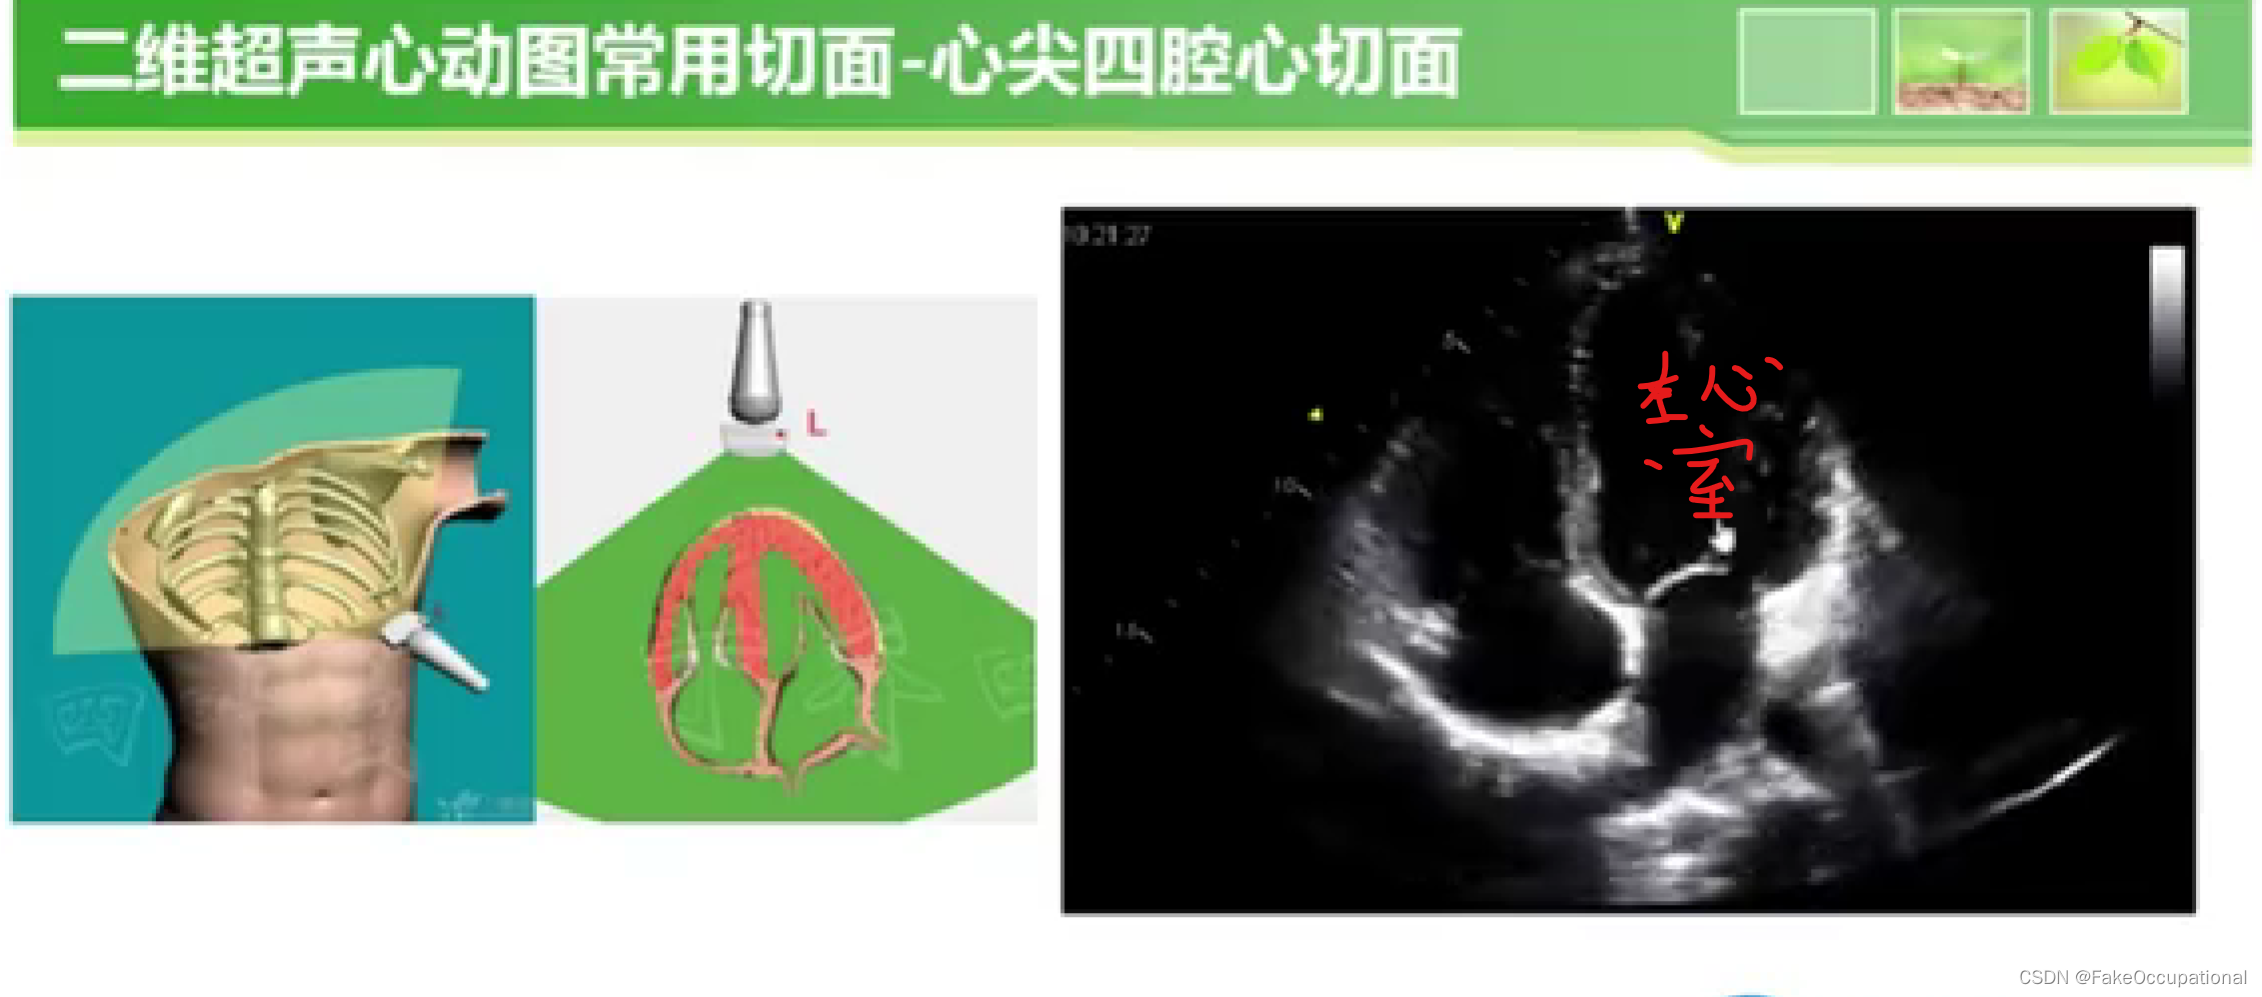

超声心动图检查方法

瓣膜病超声诊断